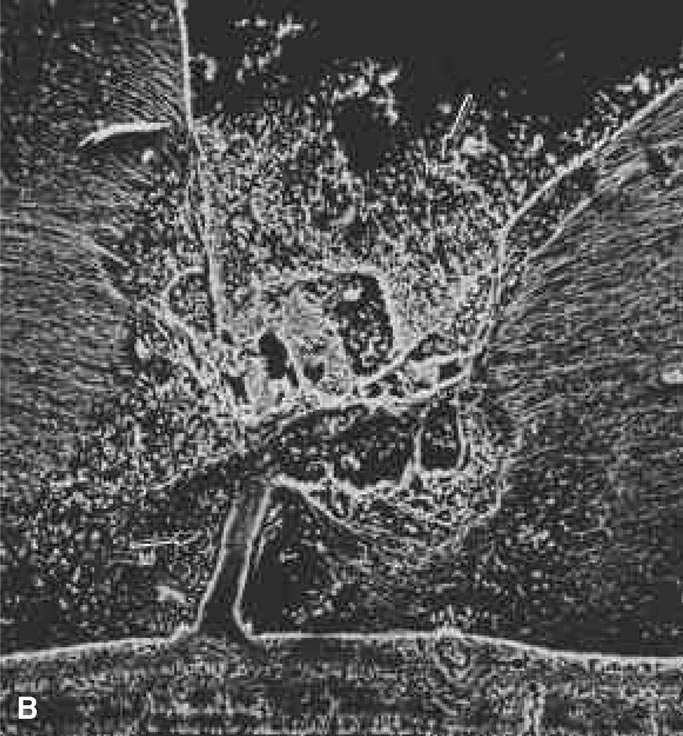

Persistent hyperplastic primary vitreous (PHPV) was first described by Reese28 as a congenital malformation of the anterior portion of the primary vitreous appearing as a plaque of retrolental fibrovascular connective tissue. This tissue is adherent to the posterior lens capsule and extends laterally to attach to the ciliary processes, which are elongated and displaced centrally. Although 90% of cases are unilateral, many of the fellow eyes have Mittendorf's dot or other anomaly of anterior vitreous development.29 A persistent hyaloid artery, often still perfused with blood, arises from the posterior aspect of the retrolental plaque in the affected eye. In severe forms, there is microphthalmos with anterior displacement of the lens-iris diaphragm, shallowing of the anterior chamber, and secondary glaucoma. PHPV is believed to arise from abnormal regression and hyperplasia of the primary vitreous.28 Experimental data suggest that the abnormality begins at the 17-mm stage of embryonic development.30 The hyperplastic features result from generalized hyperplasia of retinal astrocytes and a separate component of glial hyperplasia arising from the optic nerve head.31 The fibrous component of the PHPV membrane is presumably synthesized by these astrocytes and glial cells.32 A recent case report with clinicopathologic correlation found that collagen fibrils in this fibrous tissue had diameters of 40 to 50 nm with a cross-striation periodicity of 65 nm. The investigators concluded that the collagen fibrils differed from those of the primary vitreous and suggested that they arose either from a different population of cells or were the result of abnormal metabolism by the same cells that synthesize vitreous collagen.33

The retina is usually not involved in anterior PHPV. Indeed, previous studies have suggested that the anterior form is due to a primary defect in lens development and that vitreous changes are all secondary.34 This postulate has never been substantiated. There are rare instances of posterior PHPV in which opaque connective tissue arises from Bergmeister's papilla and persistent hyaloid vessels (Fig. 1).32,35 These can cause congenital falciform folds of the retina and, if severe, can cause tentlike retinal folds, leading on rare occasions to tractional and/or rhegmatogenous retinal detachment. Font and investigators36 demonstrated the presence of adipose tissue, smooth muscle, and cartilage within the retrolental plaque and suggested that PHPV arises from metaplasia of mesenchymal elements in the primary vitreous.